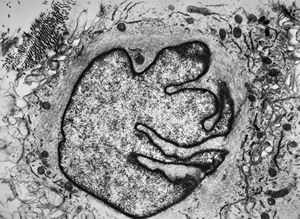

F, 37y. | mycosis fungoides … cerebriform nucleus of Sézary cell